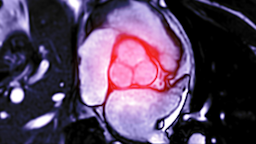

TAVR (usually pronounced “tavver”) is short for transcatheter aortic valve replacement. A minimally invasive procedure, it’s a way to replace a failing aortic valve through an artery in your leg.

TAVR was designed for these older adults. Instead of a large incision in the chest, TAVR requires only a small cut near the groin area. An interventional cardiologist, usually with a heart surgeon also present, performs the procedure.

During the procedure, the doctor attaches the new valve to a catheter, a small, flexible tube that fits through the femoral artery. Then, using imaging, they guide the catheter to the heart, where they inflate the new valve like a balloon.